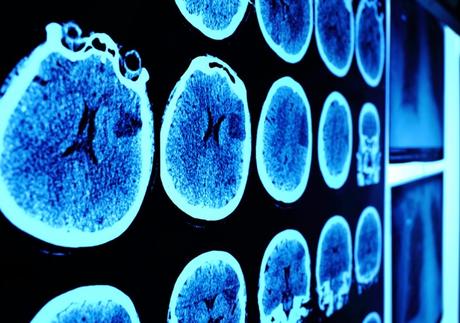

El trastorno por estrés postraumático (TEPT), afectaría de manera diferente los cerebros de niños y niñas, según un nuevo estudio de escaneo cerebral. El mismo halló diferencias estructurales en ambos sexos, en una parte de la ínsula, una región que detecta las señales del cuerpo y procesa emociones y empatía. A su vez, esta zona se encarga también de integrar sentimientos y acciones.

El equipo de investigadores realizó exploraciones de resonancia magnética en los cerebros de 59 participantes, todos jóvenes de entre 9 y 17 años de edad. De ellos, 30 (14 niñas y 16 niños) exhibían síntomas traumáticos. El grupo control, comprendido por 15 niñas y 14 niños, no los presentaban. Tanto los niños que sufrieron traumas como el grupo control, no poseían diferencias significativas en cuanto a edades y coeficientes intelectuales.

Los resultados de las resonancias no evidenciaron diferencias en la estructura cerebral entre niños y niñas en el grupo control. No obstante, entre los grupos de niños y niñas que habían sufrido distintos traumas, se hallaron diferencias en una porción de la ínsula. Esta región del cerebro tenía un mayor volumen en los niños traumatizados que en los del grupo control. Además, el volumen y la superficie de la región fueron menores en las niñas con traumatismo que entre las niñas del grupo control.